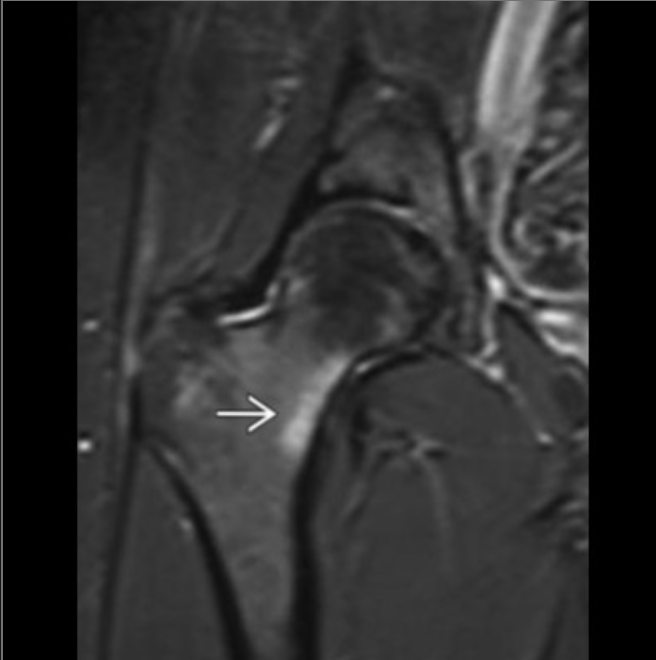

what is this structure

lateral femoral condylar recess OR condylopatellar sulcus

so its the left femoral condyle

if this is >2mm it is suggestive of ACL injury